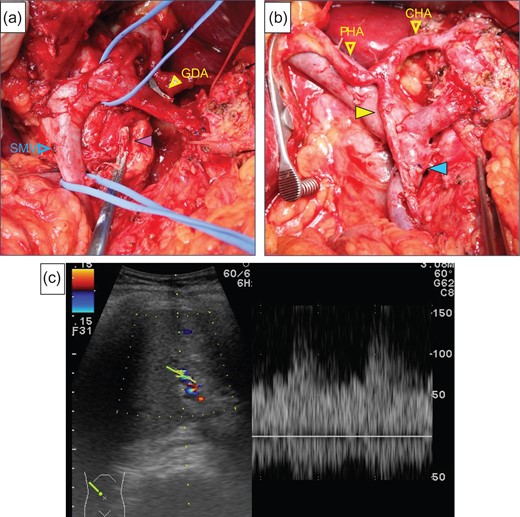

After laparotomy we identified the MAL, which had compressed the origin of the CA (Fig. 2a), and Doppler ultrasonography showed that the hepatic arterial flow was hepatopetal, but the common hepatic arterial flow was hepatofugal (no record available). First, the MAL was divided (Fig. 2b). After clamping the GDA (Fig. 2c), the hepatic arterial flow was not satisfactory (Fig. 2d). We continued the operation under GDA clamping. Finally, the specimen was connected only by the IPDA, SMV and GDA. The IPDA and aneurysm were ligated and divided (Fig. 3a). At this time, 92 min after clamping the GDA, however, the hepatic arterial flow was not improved. We were able to preserve the GDA 10 mm from its root, we divided the GDA and SMV and extracted the specimen. Arterial reconstruction by end-to-end anastomosis of the GDA and MCA was performed by plastic surgeons (Fig. 3b). After reconstruction, the hepatic arterial signal was improved (Fig. 3c).

(a) The median arcuate ligament (green arrow) compressed the CA. (b) Compression of the origin of the CA by the ligament was released. (c) The image shows that the GDA was clamped. (d) We checked the hepatic artery flow under GDA clamping, but the flow had not improved satisfactory.

(a) The purple arrow indicates the stump of the aneurysm. (b) The image was after reconstruction by end-to-end anastomosis of the GDA and the MCA (yellow arrow). The blue arrow indicates the anastomotic part of the SMV. (c) We checked the hepatic arterial flow after reconstruction, the hepatic arterial signal had increased.